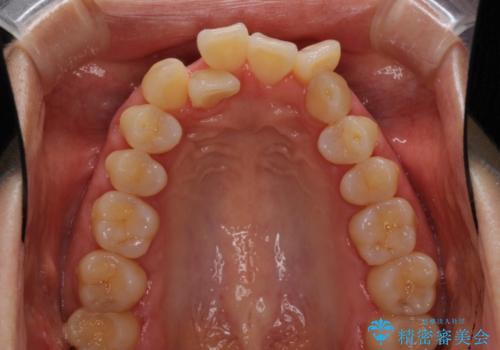

前歯のデコボコを治したい 費用を抑えた抜歯矯正

- 上下前歯のでこぼこを気にされ、矯正治療を希望された患者様です。

通常であれば、上下顎左右小臼歯各1歯の合計4本を抜歯しますが、歯肉退縮の著しい下顎前歯を抜歯して欲しいという患者様の強い希望により、上顎のみ左右小臼歯2歯を、下顎は前歯を1歯を抜歯することとしました。

抜歯する歯を変更したため奥歯の咬合はアンバランスとなりましたが、前歯は綺麗に整い、歯肉退縮も回避できました。